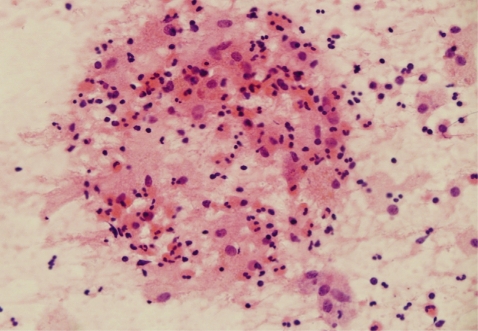

On July, the patient revisited our department because of hemoptysis and chest discomfort. A roentgenogram and CT conducted at that time showed an approximately 3.2×2.8 cm heterogeneously enhanced mass-like consolidation in the anterior segment of the right upper lobe, which was attached to the mediastinal pleura (Fig. 1). The patient underwent a percutaneous needle biopsy of this lung lesion. The histologic findings showed abundant inflammatory cells, including many eosinophils, some granulomas, and necrotic cellular debris (Fig. 2). Parasitological examination of the stool and sputum showed negative results. Triclabendazole-resistant paragonimiasis was strongly suspected on the basis of the persistent eosinophilia (WBC 6.05×103 cells/mm3, eosinophils 27%), radiological findings of the lung (Fig. 1), and histologic findings (Fig. 2). The P. westermani-specific IgG titer (OD: 0.77) was not decreased compared with that noted in October, 2008 (Fig. 3).